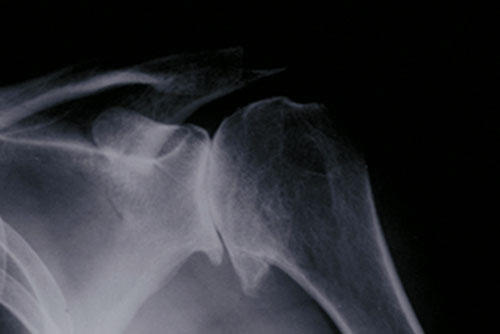

Fig. 1: X-ray showing osteoarthritis of the shoulder joint

Usually an X-ray will show the degree of articular cartilage loss and the presence of arthritis. Since cartilage does not show on an X-ray, in a normal joint its presence is demonstrated by a “space” between ball and socket. As the cartilage disappears, the space narrows on an X-ray, and in the end stage, the bone of the ball can be seen directly against the bone of the socket. In addition, bone spurs (osteophytes) which develop around the joint margins are frequently seen in some types of arthritis.